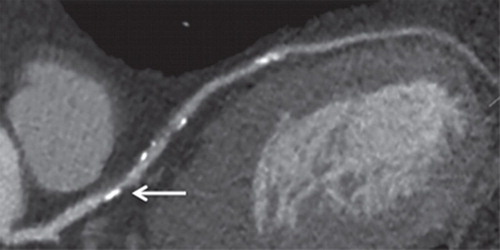

Tratamiento a valores objetivo o de alta intensidad con estatinas en pacientes con enfermedad de las arterias coronarias

En este ensayo clínico aleatorizado, entre los pacientes con enfermedad de las arterias coronarias, una estrategia de LDL-C de 50 a 70 mg/dL como meta no fue inferior a un tratamiento de alta intensidad con estatinas para el desenlace compuesto de 3 años de muerte, infarto de miocardio , accidente cerebrovascular o revascularización coronaria. Estos hallazgos brindan evidencia adicional que respalda la idoneidad de una estrategia de tratamiento con cifras objetivo que puede permitir un enfoque personalizado teniendo en cuenta la variabilidad individual en la respuesta farmacológica a la terapia con estatinas. JAMA.  6 de marzo de 2023.